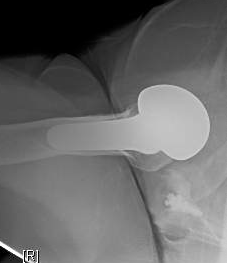

It is of note that the problem was not seen on the AP view, but the axillary view showed the shoulder to be anteriorly unstable.

This particular system allowed the opportunity to replace the anatomic glenoid prosthesis with a baseplate and glenosphere and the opportunity to put a humeral cup on the stem without having to remove the securely fixed humeral body.